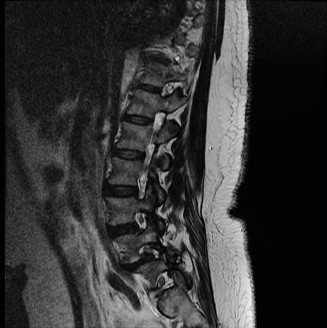

Radiographic and Computed Tomography Evaluation

Initial trauma radiographs demonstrated a loss of anterior and middle column height at L1, with a focal kyphotic deformity. However, plain films are vastly insufficient for definitive surgical planning in thoracolumbar trauma. A high-resolution, fine-cut Computed Tomography (CT) scan of the entire spine was obtained. The CT images confirmed an L1 burst fracture with severe comminution of the vertebral body. Sagittal and axial reconstructions revealed 50% canal compromise secondary to a large retropulsed bone fragment originating from the posterosuperior aspect of the L1 vertebral body. Furthermore, the CT demonstrated 25 degrees of segmental kyphosis measured from the superior endplate of T12 to the inferior endplate of L1.

A critical finding on the axial CT slices was a vertical, split fracture propagating through the L1 lamina. This is a highly significant morphological feature. A lamina fracture in the setting of a burst fracture with retropulsion strongly correlates with a dural tear and potential entrapment of the cauda equina nerve roots. When the vertebral body bursts posteriorly, the pedicles are driven outward, and the lamina fractures as the spinal canal attempts to expand to accommodate the retropulsed bone. If the dura is lacerated, nerve roots can herniate through the dural defect and become incarcerated in the laminar fracture site.

Magnetic Resonance Imaging and the Posterior Ligamentous Complex

To definitively assess the integrity of the soft tissue stabilizers and the neural elements, a Magnetic Resonance Imaging (MRI) scan without contrast was performed. Historically, textbooks propagated the "50-50-25 rule," suggesting that a burst fracture was inherently unstable if it exhibited >50% canal compromise, >50% loss of vertebral body height, or >25 degrees of kyphosis. Modern spine trauma surgery has largely debunked this rigid radiographic dogma. We now understand that these bony metrics alone do not dictate mechanical instability. The true arbiter of stability is the Posterior Ligamentous Complex (PLC).

The MRI, particularly the Short Tau Inversion Recovery (STIR) and T2-weighted sagittal sequences, provided the definitive diagnosis. The images demonstrated profound hyperintensity and discontinuity of the ligamentum flavum, the interspinous ligaments, and the supraspinous ligaments at the T12-L1 level. The facet joint capsules were also disrupted, indicated by fluid within the joints. This complete failure of the PLC means the posterior tension band is gone. Regardless of the bony parameters, this spine cannot resist physiological flexion loads. If treated non-operatively, this injury will inevitably lead to progressive kyphosis, delayed neurological deficit, and intractable pain.